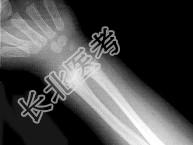

- 单项选择题男,2岁, 关节肿胀,结合图像, 最可能的诊断是 ( )

A、肾性骨病

B、黏多糖贮积症

C、维生素D缺乏症

D、维生素C缺乏症

E、维生素D过多症